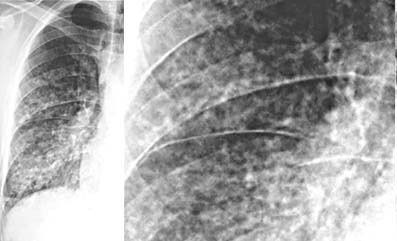

With an indistinct interstital lung pattern, lung volume may be _____ because alveoli are unable to fully expand against ______ ______. Interstitial connective tissue commonly thickens and becomes more opaque, creating fine, indistinct, linear markings described as “_____” or “____” in appearance.

smaller

interstitial infiltrates

reticular or lacey

As interstitial dz resolves or becomes chronic and less active, reticular markings become thinner and more distinct and vascular margins become better defined.

Generalized interstitial thickening= linear (“reticular”)

Discrete interstitial thickening= nodules

Interstitial and alveolar filling= silhouette